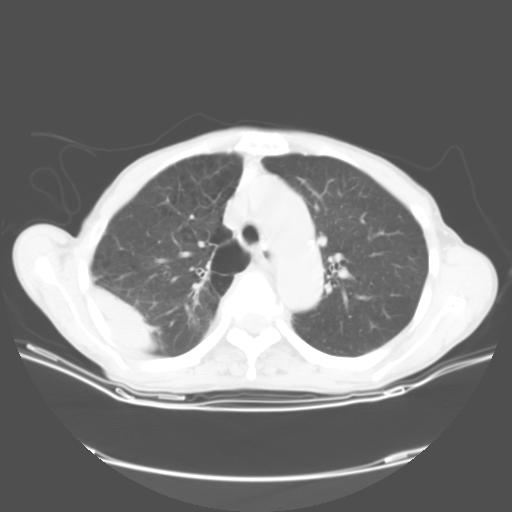

女,72岁,咳嗽一周余,突发右下肢无力二天。

pe:bp-140、80mmhg,精神可,伸舌居中,右上肢肌力正常,右下肢肌力0级,巴氏征+

来院做头颅+胸部ct平扫

遂加作增强:

胸部病变平扫35hu,增强强化至70hu

这个病人首先是胸部病变的定位到底是肺内还是肺外。仔细观察块影位于胸膜下,与胸膜间有透亮带,且近端血管未见明显推移而是引流样改变,形态分叶,说明这个病灶位于肺内胸膜下。很可能是腺癌,腺癌最易致颅内高密度转移灶。局部胸膜有侵犯。

本例颅内见多发大小不等高密度灶,有强化及水肿;另外,胸锁关节层面可能是第四胸椎及右侧肋骨起始部骨质欠连续,椎旁软组织肿胀,建议调骨窗观察。

诊断:右下肺癌伴颅内、胸椎、肋骨转移可能性最大。